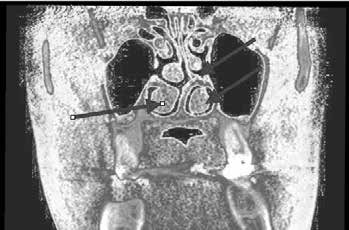

Trigeminal neuropathy can have many origins such as a neoplastic growth compressing the nerve as it leaves the pons and before it leaves the cranium through either the foramen rotundum (maxillary division, blue arrow) or foramen ovale (mandibular division, green arrrow), see Figure 2. Tumours, usually posterior fossa meningiomas or neuromas, are found in 2% of patients who present with typical TGN [5]. Surgical excision is indicated for these conditions as diagnosed via MRI.

Another source of trigeminal neuralgia can be enlargement of the middle meningeal artery that can compress the mandibular division as it leaves the skull through the foramen ovale. The middle meningeal artery is a branch of the maxillary artery in the infratemporal fossa. It enters the skull through the foramen spinosum (yellow arrow Figure 2), and is within the dura mater lining the cranial cavity. The critical abnormality is vascular contact at the dorsal root entry zone, rather than more distally; such is seen in 3–12% of trigeminal nerves at autopsy [6,7]. Brain Surgery (microvascular decompression), is necessary to treat this condition.